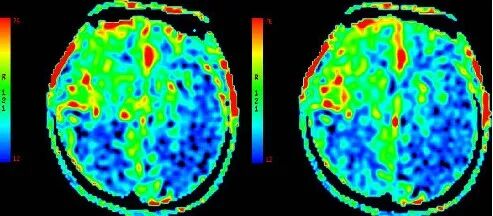

ASL

重要影像结论:3月前ASL示:左侧额颞顶枕叶、右侧颞枕叶血流灌注量明显减低。

重要影像结论:ASL示:原左侧额颞顶枕叶、右侧颞枕顶叶血流灌注量明显减低区范围较3月前明显增大。